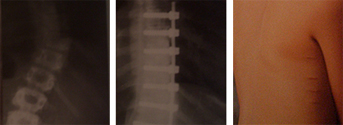

Escoliosis tratada por técnica mínimamente invasiva con imágenes radiográficas y de las cicatrices a los dos años de la intervención.